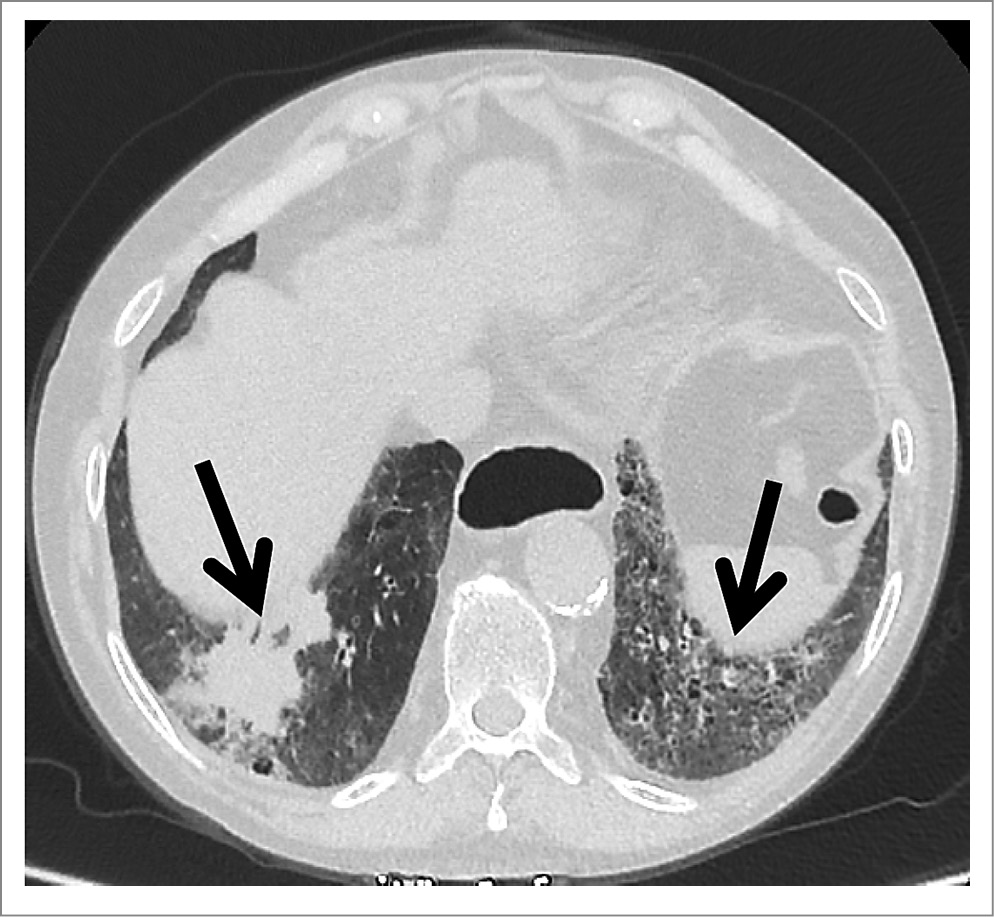

При КТ органов грудной клетки (ОГК) обнаружено образование нижней доли правого легкого размерами 55×40 мм с неровными нечеткими лучистыми контурами. В верхней доле правого легкого визуализировались два кольцевидных очага размером 4,5 мм. В нижних долях обоих легких, субплевральных отделах верхних долей и в средней доле справа определялись участки формирования сотового легкого. Медиастинальная лимфаденопатия. Деструкция VII ребра справа, вероятно, вторичного характера. При предыдущем исследовании от 25.04.2023 очаговые изменения не выявлялись, имелись лишь проявления интерстициального поражения легких (рис. 2, 3).

Рис. 2. КТ ОГК. Визуализируются образование нижней доли правого легкого, участки формирования сотового легкого в нижних отделах обоих легких, деструкция VII ребра справа.

Рис. 3. КТ ОГК в сагиттальной плоскости.